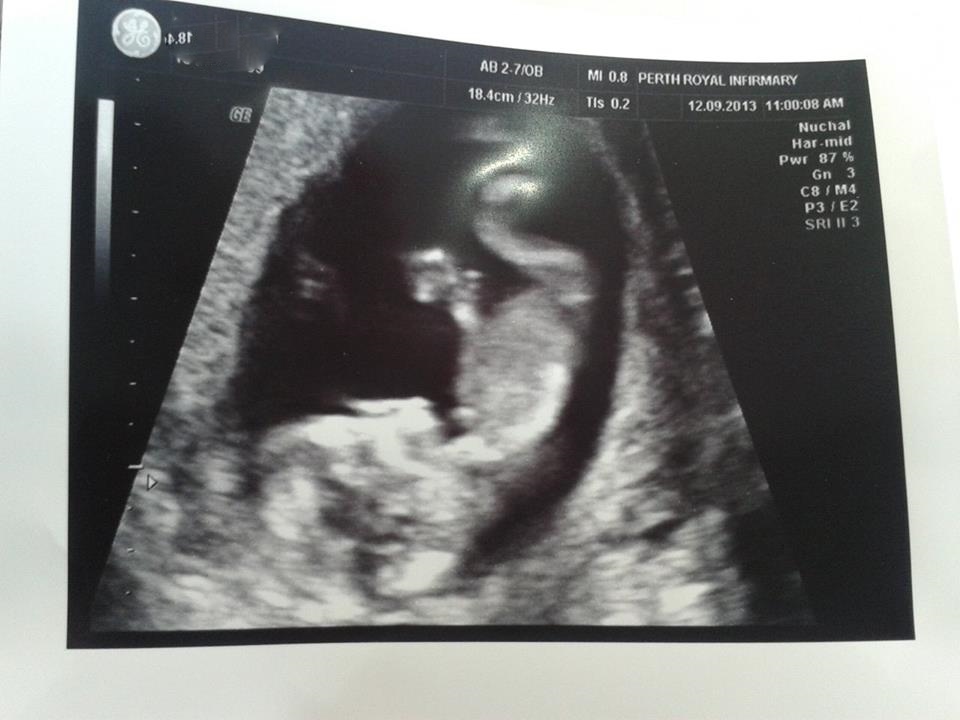

Attachment 14016 Attachment 14017 baby was quite happy upside down and showing off acrobatic skills!

I do not see a nub.